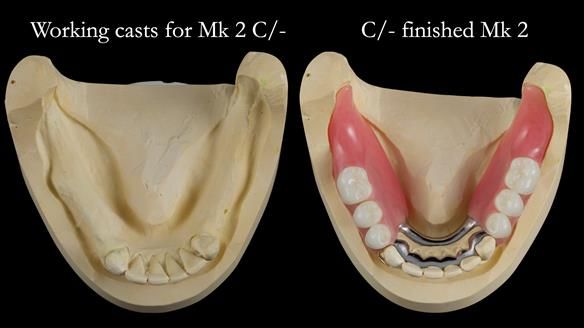

This newsletter describes the full protocol workflow of a complete upper denture and a lower partial denture for Jo.

The clinical situation and treatment process is shown in detail below. I provided the clinical work. Rowan Garstang provided the technical work. This treatment took 25 visits over a period of 12 months.